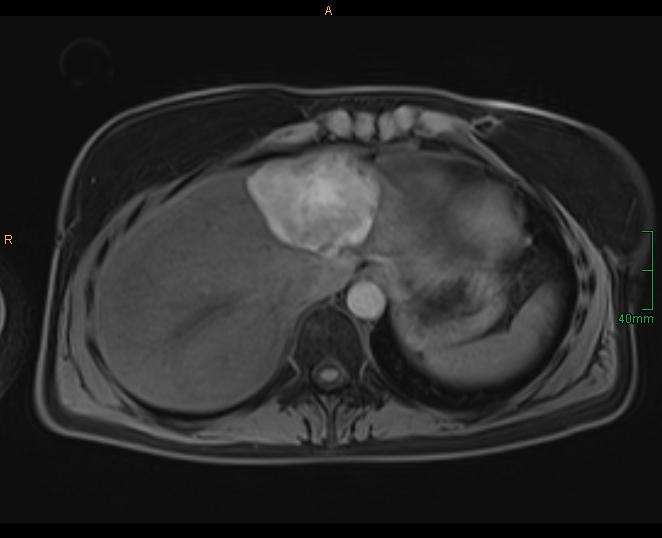

Figure 1D: MRI 26 months after SRFA showing complete ablation and shrinkage of ablation zone to 6.5 cm.

In the meantime, we have treated > 900 patients with > 3000 liver tumors in > 1500 sessions and collected them in our prospective SRFA registry. After bridging therapy with SRFA for liver transplantation, complete histopathological response was found in 183 of 188 treated lesions (97.3%) and in 50 of 52 lesions > 3cm (96.2%) 2. In a recent paper reporting the results after SRFA of very large tumors (> 8 cm) 3 (Figure 1) and in other studies including primary and secondary liver tumors the short- and long-term outcomes after SRFA were comparable to HR.